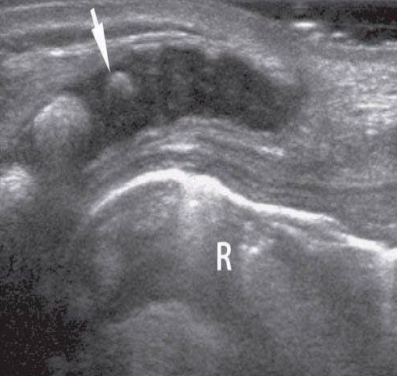

white arrow

end of thecal sac (about s2)

partially calcified coccyx

r

rectum filled with air